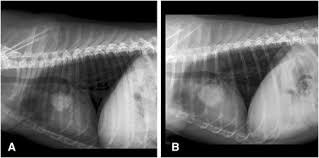

Can Roundup Cause Cancer In Dogs Pintas Mullins Law Firm from www.pintas.com To help you make an informed decision on putting your dog to sleep, let us discuss the signs of end stage lung cancer in dogs. Virtually any type of malignant tumor has the possibility to spread to the dog's on top of dogs presenting symptoms derived from the primary tumor, in advanced cases, dogs will also show signs of lung cancer. Early cancer detection in dogs can be tricky due to their inability to communicate with their caretakers in a clear. Detecting cancer in dogs, early warning signs of canine tumors and treatment options. The signs of metastatic lung disease are similar to those of primary lung tumors except that coughing is less common. Approximately 25 percent of pets with lung cancer may not show any clinical sign of disease at all. Primary lung cancer, or tumors originating in the lung, are relatively uncommon in dogs be aware that dogs with multiple lung masses may be the result of a fungal infection and not cancerous. Primary lung cancer is defined as tumors that originate in the lung tissue.